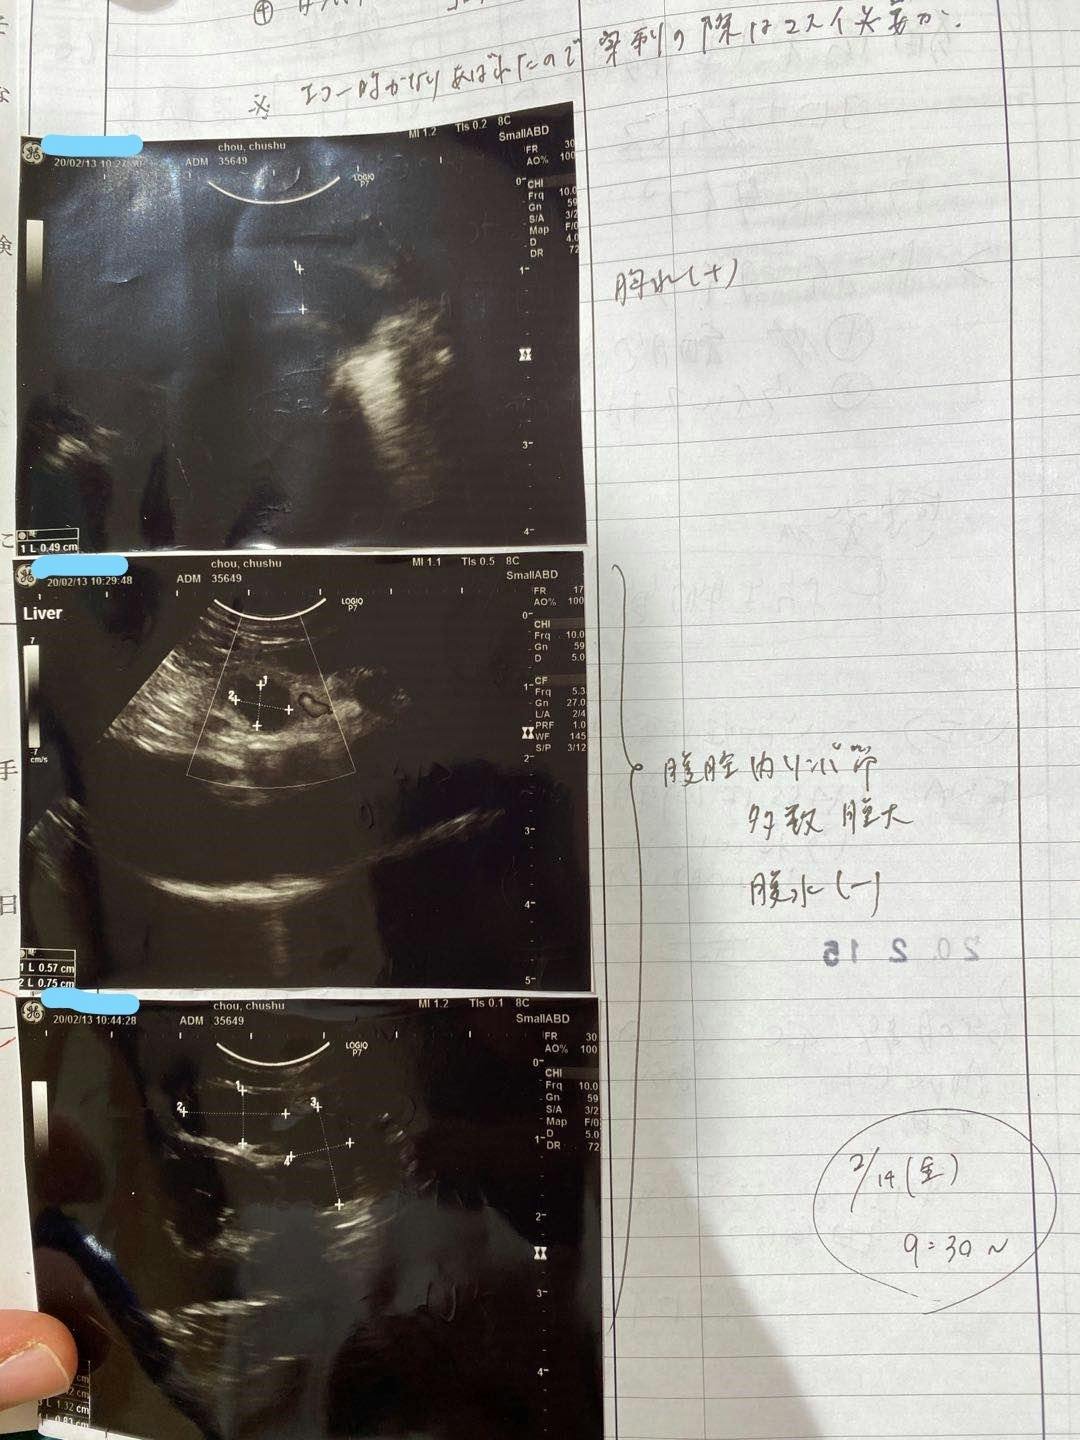

2/13去勢手術するため、身体検査をするとき、肺の中に薄い水影があって、念のため詳しい検査を行いました。

症状が軽い、判断が難しく、少し観察の時間が必要けど、最悪の場合はFIPを罹っているの可能性があると言われて、でも別の病気の可能性もあると言われました。3/9でレントゲン検査すると、水影が少し薄くになって、4月の検査も同じになって、FIPの可能性ではないかもと思います。けど、5月の検査はあまり変わらないになって、22日で急に発症になりました。前を振り返って見て、ずっと自分を責め続いている。

腹水がたまっています

肉芽腫が見つかります